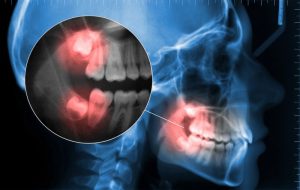

While maintaining your natural teeth is our main priority, sometimes a tooth has to be removed to preserve the health of your remaining teeth and gums. This may be due to severe decay, breakage of the tooth or overcrowding within the mouth. Impacted wisdom teeth also require extraction.